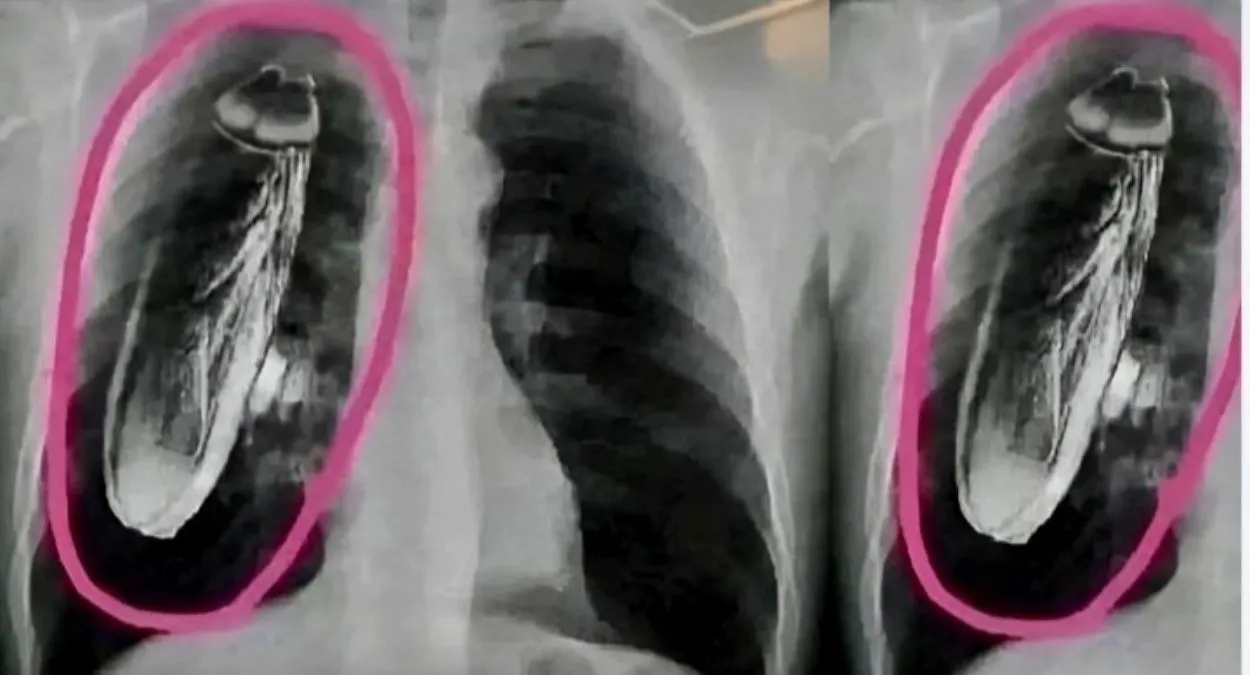

AI जेनरेटेड था इंटरनेट मीडिया पर प्रसारित सोलन अस्पताल का एक्सरे (फोटो: जागरण)

संवाद सहयोगी, सोलन। इंटरनेट मीडिया पर प्रसारित एक्सरे की तस्वीरें एआइ से जेनरेटेड हैं। यह दावा क्षेत्रीय अस्पताल सोलन के प्रबंधन ने किया है।

अस्पताल प्रबंधन का कहना है कि एक्सरे तस्वीरों में दिखने वाला तिलचट्टा (काकरोच) किसी मरीज के शरीर में नहीं, बल्कि तस्वीरों की एडिटिंग का हिस्सा है। इस पोस्ट के अलग-अलग संस्करण बद्दी और शिमला अस्पताल के नामों से भी प्रसारित किए गए, जिससे गलत सूचना और तेजी से फैल गई।

इस पोस्ट में दावा किया जा रहा है कि एक विदेशी पर्यटक के सीने में जिंदा तिलचट्टा मिला। पोस्ट में तीन एडिटिड एक्सरे कापियां लगाई गई हैं। इसमें लिखा है कि सिंगापुर के पर्यटक को सीने में दर्द हुआ, जिसके बाद वह क्षेत्रीय अस्पताल सोलन पहुंचे।

वहां एक्सरे होने के बाद कथित तौर पर उन्हें बताया कि उनके सीने में जिंदा तिलचट्टा दिखाई दे रहा है और तुरंत सिंगापुर लौटने की सलाह दी।

बाद में डॉक्टरों को पता चला कि यह तिलचट्टा मरीज के अंदर नहीं, बल्कि एक्सरे मशीन में मौजूद था।